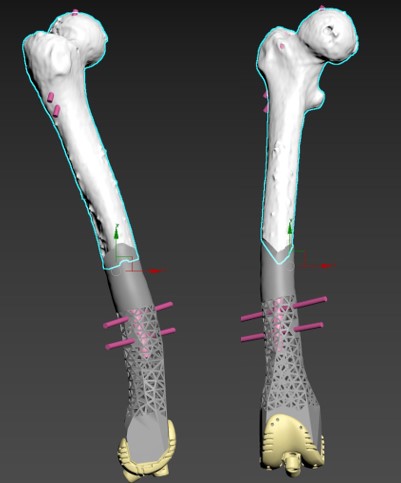

Етапи проектування онкопротезування

Хворий Г.58 остеосаркома стегнової кістки